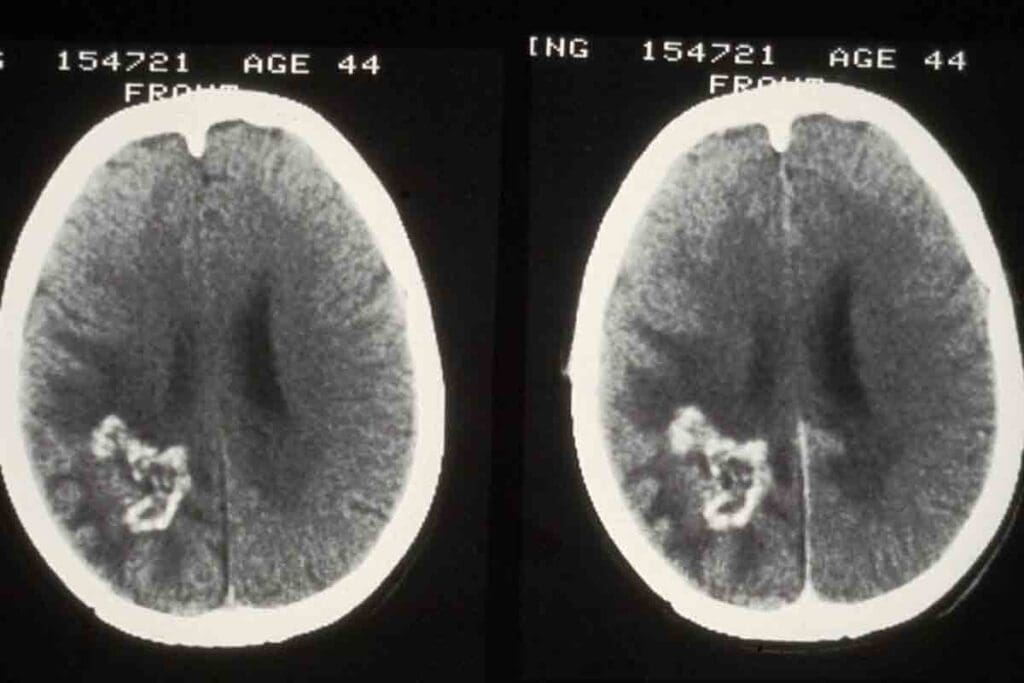

Impact of Improved Diagnostic Technologies

New diagnostic tools have changed how we study brain tumors. High-resolution imaging, like MRI and CT scans, helps us spot and understand tumors better. This leads to more accurate diagnoses and a deeper understanding of tumor biology.

Artificial intelligence is also making a big difference. It helps us classify tumors more precisely and plan treatments better. These advances are key to improving brain tumor care and research.